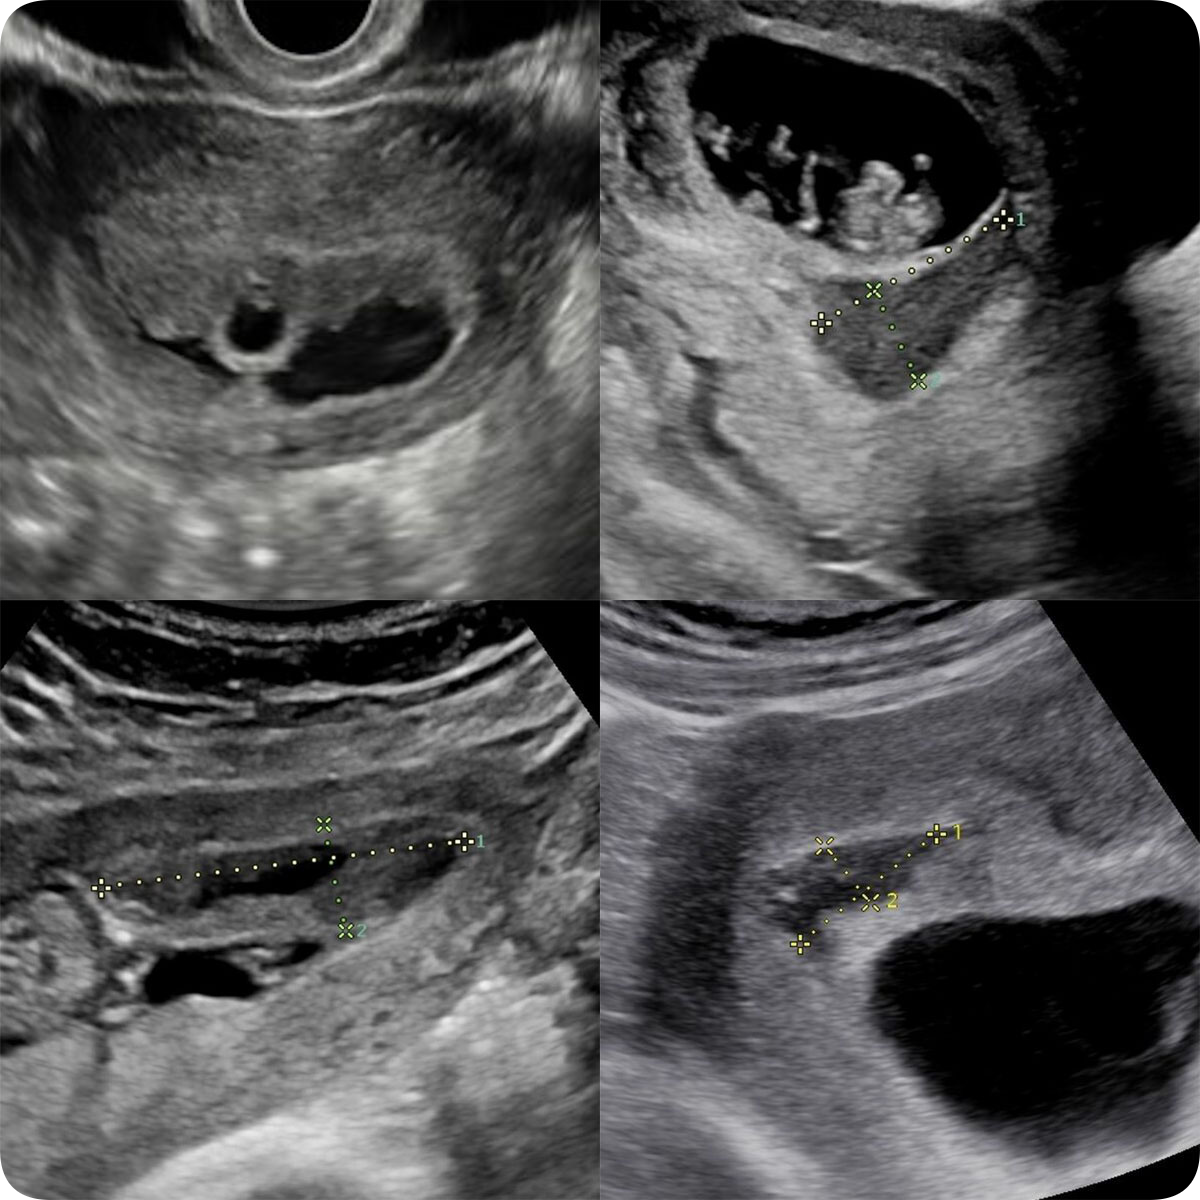

Диагностика малого срока беременности

• Плодное яйцо

• Этапы визуализации

• Условия для лучшей диагностики

• Минимальные сроки

• Ложное плодное яйцо

• Измерения ВДПЯ, КТР, ЧСС эмбриона

• Остаточная полость матки

• Патология малого срока беременности

• Беременность в рубце на матке

• Примеры, описания, заключения